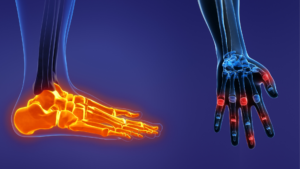

Affûtez votre analyse des douleurs de la main et du pied et orientez vos patients vers l’orthèse la plus adaptée pour un conseil expert et sécurisant au comptoir.